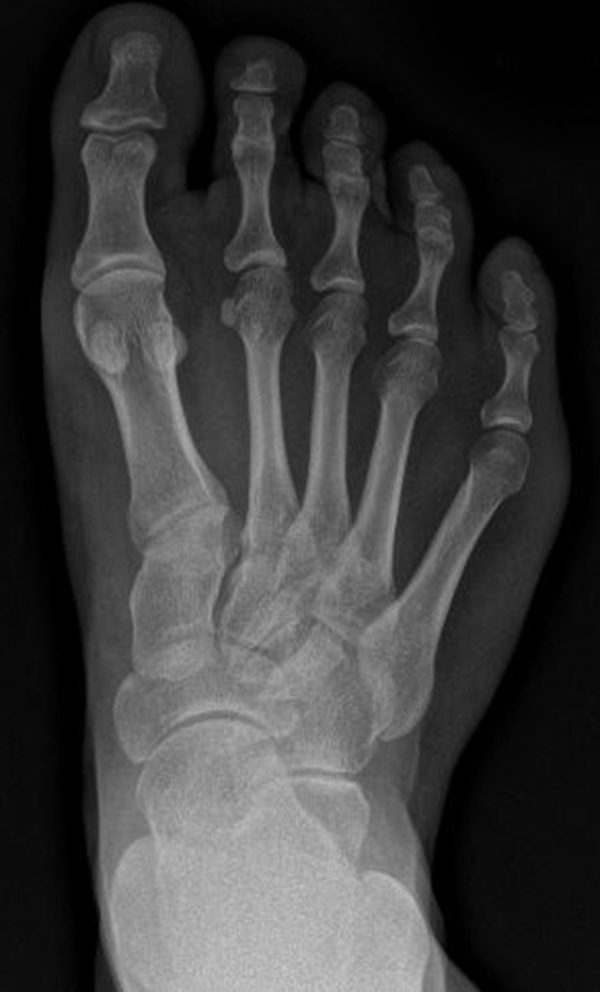

Abb. 7 a, b: Typ II Deformität mit prä- (a) und postoperativem Röntgenbild (b) mit K-Draht Osteosynthese und gleichzeitiger Hallux valgus Korrektur.

Abb. 8 a, b, c: Typ III Deformität mit prä- (a) und postoperativem Röntgenbild (b, c) mit Schrauben-Osteosynthese.

Abb. 9 a, b: Typ III Deformität mit prä- (a) und postoperativem Röntgenbild (b).